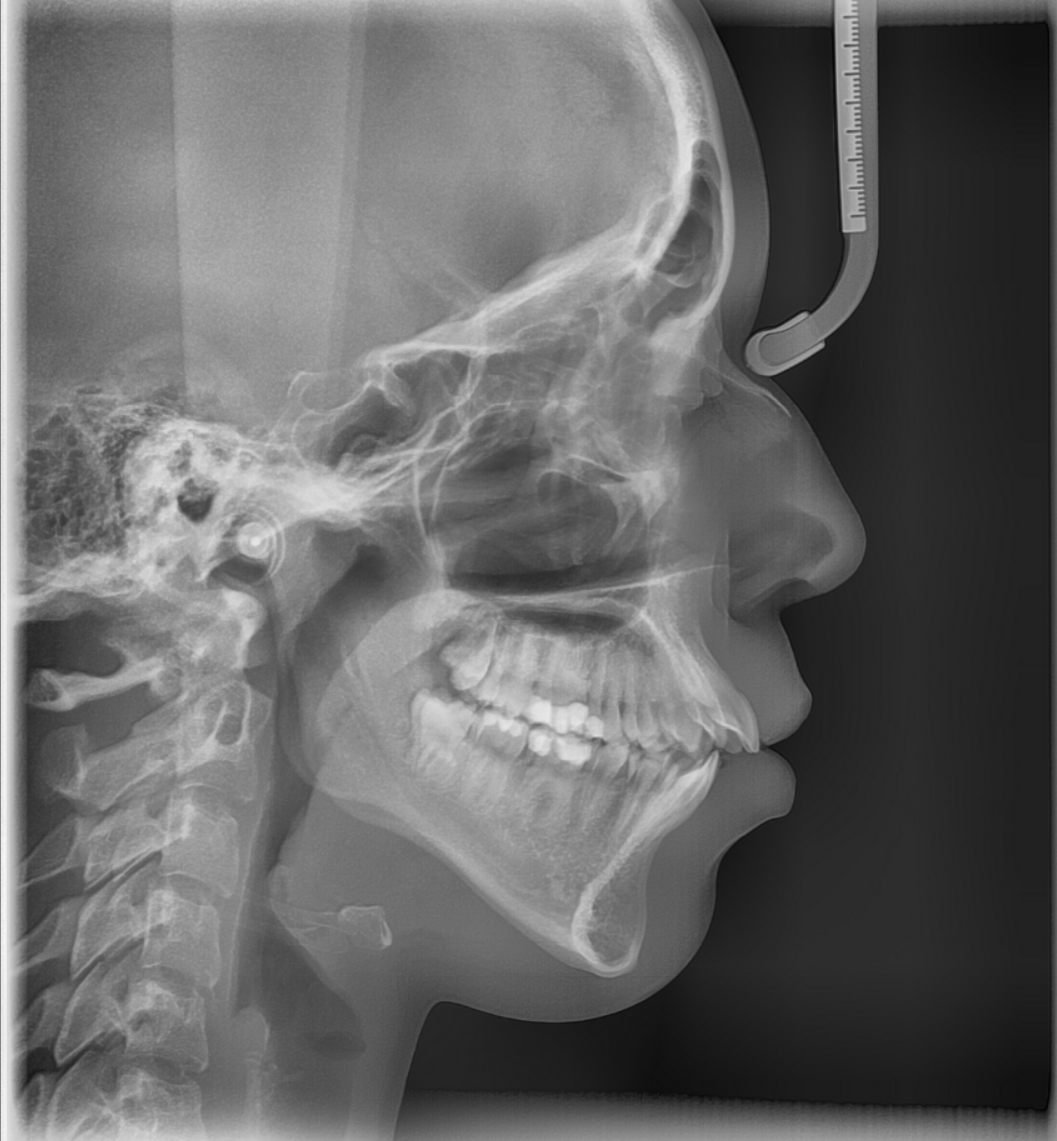

Das Fernröntgenseitenbild

Bei einer kieferorthopädischen Behandlung werden Zähne in eine neue Position verschoben. Vorher ist es wichtig zu wissen, wie die Zähne im Knochen verankert sind. Zähne dürfen immer nur so weit bewegt werden, dass noch ausreichend Knochen und ein gesunder Zahnhalteapparat vorhanden sind. Andernfalls könnte sich das Zahnfleisch zurückziehen und der Zahnhalteapparat geschädigt werden. Im schlimmsten Fall können sich Zähne lockern oder sogar verloren gehen. Weil dies auf der Panorama-Aufnahme nicht ausreichend beurteilt werden kann, ist noch ein zweites Röntgenbild, das sogenannte Fernröntgenseitenbild (FRS), nötig.

Warum ein Fernröntgenseitenbild?

Bei Kindern und Jugendlichen gibt das Bild Auskunft über die Wachstumsrichtung des Kiefers. Dieses Wissen ist entscheidend für die Planung von Therapiezeit und -art sowie die Auswahl der Zahnspange.

Anhand der seitlichen zweidimensionalen Röntgenaufnahme beurteilt dr. Anna Schroen, wie die Kiefer zueinander positioniert sind. Sie erkennt, wie die Frontzähne von der Seite aus betrachtet im Knochen stehen. Dadurch ist es möglich zu beurteilen, wie dick die Knochenschicht ist, die die Zahnwurzeln umgibt. Davon kann sie ableiten, welche Zahnverschiebungen sicher möglich sind - und vor allem, welche nicht.